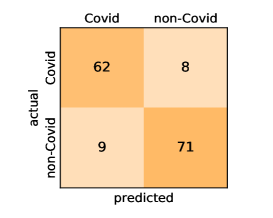

Here, we present and discuss the obtained results for detecting COVID-19 on the considered CT image datasets with different deep networks. We report the quantitative results along with the confusion matrices for every single architecture of the adopted networks.

On the SARS-CoV-2 CT dataset, ResNet101 achieves the best overall performance with respect to almost all evaluation metrics, with an average accuracy and F1-score of and , respectively. The model also achieves an average sensitivity rate of indicating that, on average, only two COVID-19 images are falsely predicted as negatives. It is also powerful enough to correctly identify all Non-COVID-19 cases with only one false positive resulting a specificity rate of . The highest sensitivity score of is achieved by the InceptionV3 model, where only one COVID-19 image is falsely predicted as negative on average. The SqueezeNet model obtains the lowest performance with respect to all evaluation metrics with a fairly acceptable average accuracy and sensitivity scores of and , respectively. Also the ShuffleNet architecture obtains satisfactory performance with approximately improvements on average for all metrics compared with SqueezeNet. Although the results obtained by these models are inferior compared with the rest of models, but they are more efficient. This matches their main objective of reducing the computational costs rather than improving their visual recognition abilities. The rest of models achieve competitive performance and very promising results with slight performance differences. Comparing the different variants of ResNet and DenseNet, we can see that the deeper variants from each architecture yield a slightly better performance. The deeper ResNet101 and ResNeXt101 show a marginal gain in performance compared with their shallower counterparts. The details about class-wise results for each model are summarized in the confusion matrices in Figure 9.